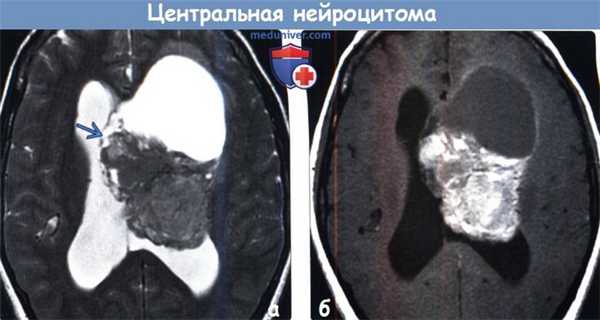

• Предполагайте центральную нейроцитому при выявлении у молодого взрослого пациента объемного образования «пенистой», «перистой» или солидной структуры, расположенного интравентрикулярно вблизи отверстия Монро(а) На рисунке аксиального среза показано отграниченное от окружающих структур «пенистое» объемное образование дольчатой структуры, прилежащее к прозрачной перегородке. Расширение желудочка обусловлено обструкцией отверстия Монро. Это классическая картина центральной нейроцитомы. Тотальная хирургическая резекция часто позволяет добиться излечения данной опухоли II степени злокачественности по классификации ВОЗ (grade II).

(б) Бесконтрастная КТ, аксиальный срез: в боковом желудочке, прилегая к прозрачной перегородке, определяется объемное образование гетерогенной структуры (с кистозным и солидным компонентами). Наблюдается вторичная гидроцефалия, что характерно для центральной нейроцитомы. (а) МРТ, Т2-ВИ, аксиальный срез: у пациента 20 лет с жалобами на головные боли определяется объемное образование преимущественно солидной структуры, расположенное в теле бокового желудочка и имеющее связь с прозрачной перегородкой. В структуре образования определяются заметные участки потери сигнала за счет эффекта потока.

(б) МРТ, постконтрастное Т1-ВИ, аксиальный срез: у того же пациента определяется диффузное контрастирование объемного образования. При хирургической резекции была диагностирована центральная нейроцитома. Дифференциальный диагноз при визуализации проводится с субэпендимальной гигантоклеточной астроцитомой, субэпендимомой и менингиомой.в) Дифференциальная диагностика: